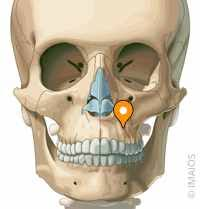

If it is lower down on the maxilla as the first two images suggest then it would be easier to check but just sticking your finger in your mouth and feeling if the bone above your teeth slants back slightly

If it is lower down on the maxilla as the first two images suggest then it would be easier to check but just sticking your finger in your mouth and feeling if the bone above your teeth slants back slightly